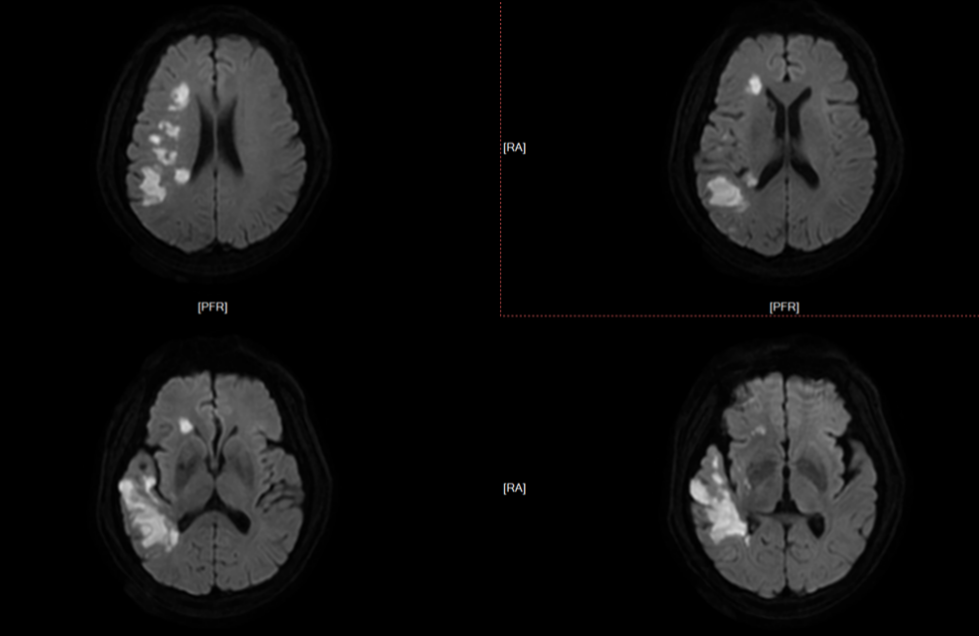

患者为一名65岁男性,3月16日突发左侧肢体活动障碍,次日症状加重,并出现反应迟钝、言语不清、口角歪斜等新发症状后转至苏大附四院继续治疗。入院后CTA(CT血管造影术)检查提示右侧大脑中动脉水平段(R-M1)管腔完全闭塞,远段分支稀疏;CTP(脑灌注检查)则提示右侧额顶颞叶缺血性灌注异常;头颅MRI(核磁共振成像)见右侧岛叶、颞叶、右侧脑室旁及放射冠区急性脑梗死。综合检查结果,考虑到患者发病时间较长,与家属商议后予以强化内科治疗。

MRI:右侧岛叶、颞叶、右侧脑室旁及放射冠区急性脑梗死